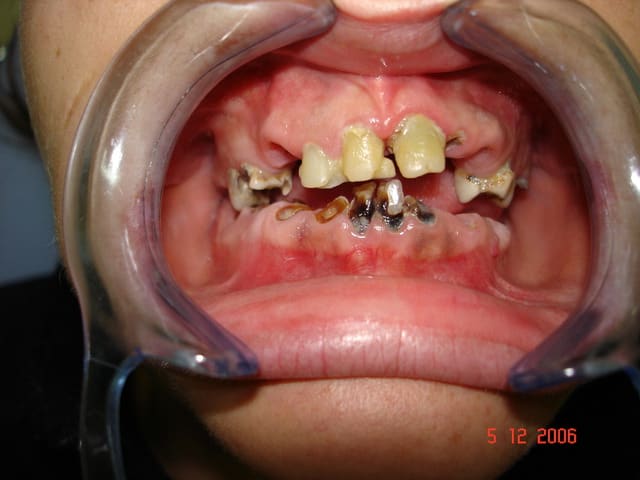

Je relance le sujet.

Patient vu en début d'année, parodontite en phase terminale, "monsieur je pense qu'il faudrait vous enlever quelques dents" (voir pano). Lui pas trop pressé apparemment.

Il revient me voir ce mois-ci pour faire sa prothèse. Je lui dit qu'il faut extraire ses dents d'abord.

Il me répond : "ah ben non, elles sont déjà tombées, mais je les garde en bouche ... en attendant!"

Et donc à chaque étape, empreinte, RIM, essayage, je demandais à monsieur d'enlever ses dents, qu'il remettait en place à la fin de la séance.

Du jamais vu pour moi, même si je suis encore jeune dans le métier!!

Fallait que je fasse partager!

petite question tu fais quoi avec ce qui reste ???(41 42 31 32 34)

il les a remises pour la photo ou tu gardes pour faire une pap ?

Je les ai gardées, il avait l'air d'y tenir...

Vu l'énergumène, il sera bien capable de les faire tenir 20 ans! Comme quoi tout est dans le mental